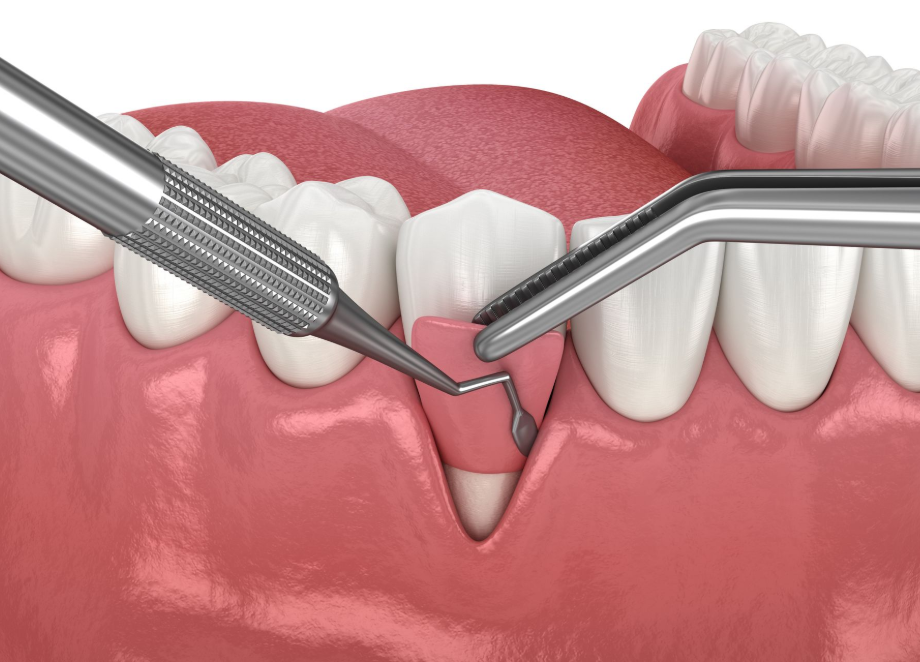

Every surgical plan begins with an assessment. We review your symptoms, examine the area, and discuss your treatment options. If oral surgery is needed, we explain the steps clearly, including what the procedure involves, how long it may take, and what recovery may look like. Your comfort is a priority, and we use gentle techniques and supportive care to help you feel at ease.

After your procedure, you will receive detailed instructions for healing, including guidance on eating, hygiene, and managing soreness. Our team remains available if questions come up during recovery, and we may recommend follow up care to make sure healing is progressing as expected.